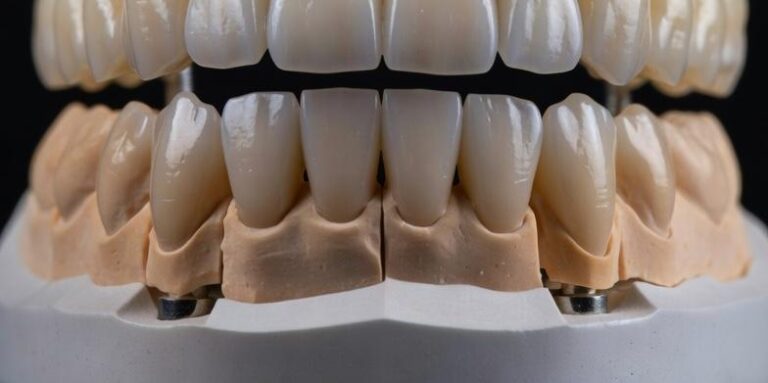

Carico Immediato a Torino: Quando È Indicato

Implantologia

Il carico immediato consente di posizionare una protesi fissa sugli impianti entro 24-48 ore dall’intervento, ma non è una soluzione adatta a…